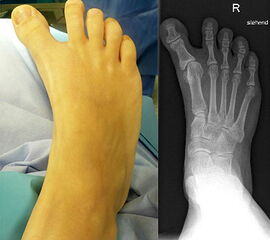

Angeborene Deformität und Fehlanlage 1. Strahl (eigenes Bildmaterial) (Vispo-Seara 1998, Hefti 1998)

Abbildung 9

Mit zunehmendem Wachstum und Alter wird die Abweichung der Großzehe zunehmend symptomatisch. Es können keine normalen Schuhe getragen werden, es entstehen kosmetisch schwerwiegende Probleme. Deshalb wird zu einer frühzeitigen Korrektur im Säuglings- und Kleinkindalter geraten 12, d. h. im 9. – 24 Lebensmonat 215.

Die Therapie ist immer operativ, wobei sich der individuelle Eingriff an der jeweiligen Dysplasie orientiert.